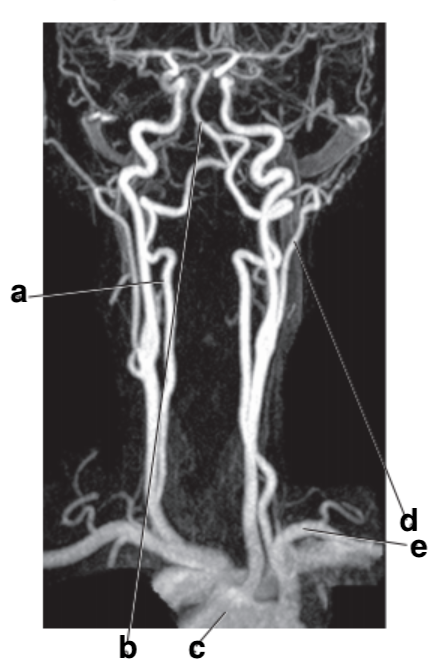

What is letter e?

Subclavian artery

Which letter is the popliteal artery?

A

Which letter is the left common carotid?

Which letter is the Right vertebral artery?

f

What is letter m?

Common carotid artery

left popliteal artery